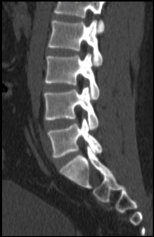

Chẩn đoán hình ảnh mô mềm tiên tiến cho vùng bụng.

Tăng cường độ tương phản I-ốt.

Hỗ trợ đánh giá an toàn cho bệnh nhân.

Đảm bảo hình ảnh chất lượng cao.